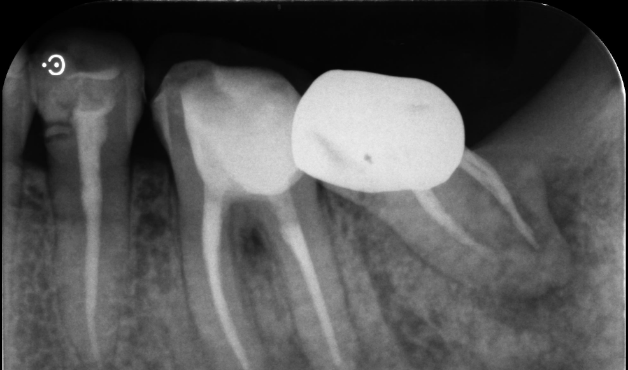

自家歯牙移植と根管治療で

天然歯を保存した症例

タップで写真の拡大ができます。

Before

Under Treatment

After

主訴

歯を残せないと言われた。インプラントは先延ばしにしたい

治療内容

自家歯牙移植 / イニシャルトリートメント(大臼歯)レジンコア

治療期間

2ヶ月

治療費用

308,000

治療の

リスク

術後しばらくしてから骨性癒着、外部吸収を起こす可能性があります。